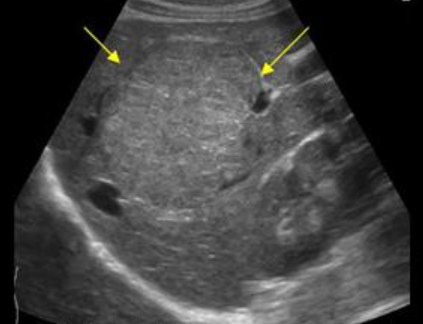

FNH의 경우 초음파소견은 다양하다. 병변은 등에코, 저에코, 고에코의 균질한 덩어리로 나타날 수 있다. 간내 혈관을 대체할 수 있는 대량 효과가 있다. 단지 18%의 사례에서만 중앙 흉터(저에코성 센터)가 존재한다. 이는 간혈관종과 매우 유사해 보인다. 또한 혈관 기형부위와 관련이 있다. 일반적으로 5cm 미만이다.

FNH (Focal Nodular hyperplasia) US finding

- spokewheel vascularity

- iso-hyperechoic mass

- hypoechoic lesion with central scar

- fatty liver